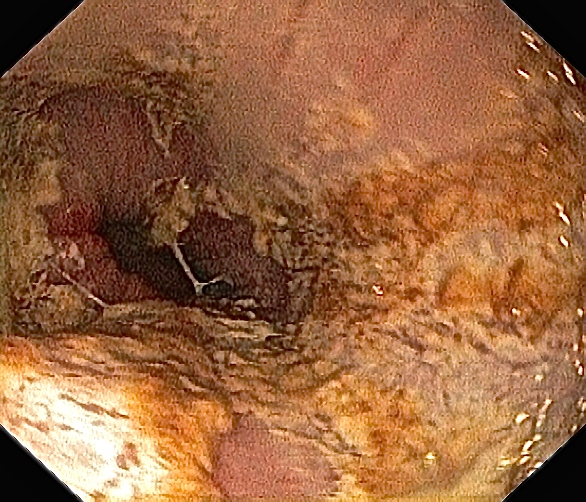

Magesekk.

Mer magesekk.

Slimhinnene var rosa, glatte og fine. Det var bare små tegn til betennelser, i motsetning til tidligere. Da har vevet vært veldig irritert og med sår pga gastritt (betennelse i magesekken) og øsofagitt (betennelse i spiserøret). Så medisinene jeg tar for dette funker. Hvorfor det er bedre nå enn før er ikke godt å si, men jeg vil tro det skyldes at jeg kaster mindre opp pga pacemakeren. Jeg skal til ny konsultasjon hos gastrolegen min neste uke, håper jeg kan få tid til å spørre litt mer inngående rundt det.